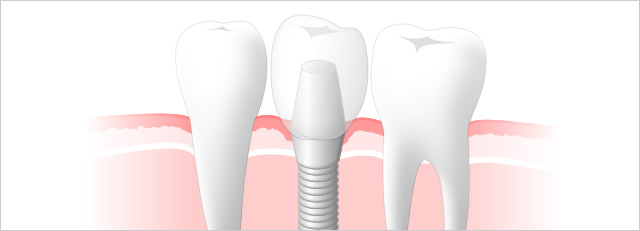

横の歯に負担がかからないインプラント治療

症状

- 1

- 横の歯に負担をかからないので、自分の歯が残ります。

- 2

- 天然歯のように顎には生理的刺激がいくた、顎の骨がやせない。

- 3

- もしインプラントがダメになっても骨は再生可能なので1本だけの治療で済みます。

そしてなにより - 4

- 噛みごたえのある食生活は幸福感を高くします。